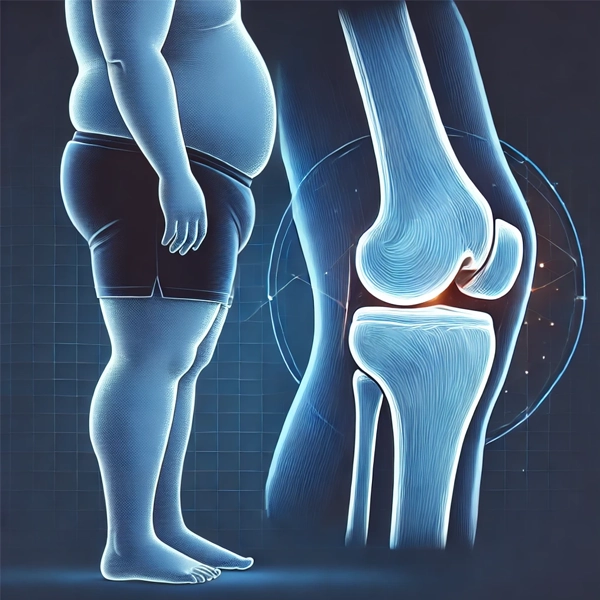

تاثیر اضافه وزن در جراحی تعویض مفصل یکی از عوامل مهمی است که در موفقیت این جراحی و روند بهبودی بیمار نمایان خواهد شد و ملموس است. اضافه وزن باعث افزایش فشار بر مفاصل، به ویژه مفصل زانو و لگن میشود و در بسیاری از موارد، دلیل اصلی ساییدگی و تخریب تدریجی آنها است.

نقش اضافه وزن در افزایش فشار روی مفاصل

اضافه وزن فشار زیادی بر مفاصل بدن، به ویژه مفاصل زانو، ران، لگن و کمر وارد میکند. هر یک کیلوگرم اضافه وزن به طور قابل توجهی بار اضافی بر این مفاصل وارد میآورد که موجب سرعت بخشیدن فرسایش و آسیب به غضروف ها و ساختارهای مفصلی میشود.

این فشار اضافی باعث التهاب، درد و مشکلات حرکتی میشود و در طول زمان به بروز مشکلات جدی مانند آرتروز و ساییدگی مفاصل منجر میگردد.

در نتیجه، افرادی که اضافه وزن دارند و دچار مشکلات مفصلی میشوند، به دلیل کاهش عملکرد مفاصل، به جراحی مانند تعویض مفصل یا جراحی های ترمیمی نیاز پیدا میکنند.

کاهش وزن فشار بر مفاصل را کاهش داده و در برخی موارد نیاز به جراحی را به تاخیر میاندازد یا از آن جلوگیری میکند. در هر صورت، مدیریت وزن و حفظ سلامت مفاصل، نقش حیاتی در پیشگیری از مشکلات جدی و جراحی های احتمالی دارد.